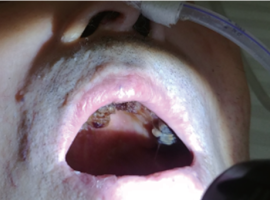

잇몸에서 피가나고 붓는 경우

잇몸에서 피가나고 붓는 경우

구강위생관리 사례